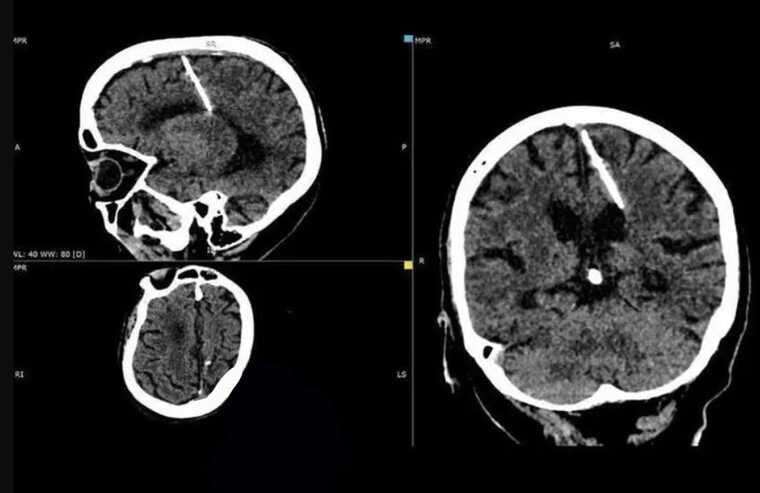

Sau khi chụp CT, các bác sĩ phát hiện ra 1 cây kim dài 3cm cắm vào bên trái não của cụ bà 80 tuổi ở vùng Sakhalin, Nga.

Hình ảnh kết quả chụp CT của cụ bà được Bộ Y tế Sakhalin công bố mới đây kèm theo lời giải thích gây sốc. Khi xem xét độ tuổi của bà lão, các bác sĩ tin rằng, chiếc kim đã được chính cha mẹ bà đưa vào não ngay sau khi bà chào đời. Nghe có vẻ không tưởng nhưng đây là việc làm khá bổ biến của các gia đình trong thời Chiến tranh thế giới thứ hai. Ở thời điểm ấy, nhiều bậc cha mẹ không đủ khả năng chăm sóc con mình nên đã đâm những chiếc kim mỏng vào não qua thóp - khe hở trên hộp sọ sẽ dần khép lại khi đứa trẻ lớn lên - để giết chết chúng. Phương pháp này không để lại dấu vết vì thóp nhanh chóng đóng lại, không để lại bằng chứng, che giấu được phương thức phạm tội.

Không rõ làm thế nào mà bà lão có thể vượt qua lưỡi hái tử thần, sống khỏe mạnh suốt 80 năm. Điều đáng chú ý hơn nữa là bà chưa bao giờ trải qua những cơn đau đầu vì có vật thể lạ trong não. Nếu không có kết quả chụp CT gần đây, bà sẽ không bao giờ biết đến sự tồn tại của cây kim dài tới 3cm trong não mình.

Các bác sĩ cho rằng, việc can thiệp phẫu thuật để rút kim ra sẽ chỉ khiến bệnh nhân gặp nguy hiểm do tuổi đã cao. Họ kết luận rằng, chiếc kim không gây nguy hiểm cho sức khỏe của bà và bà sẽ được các bác sĩ kiểm tra sức khỏe thường xuyên.